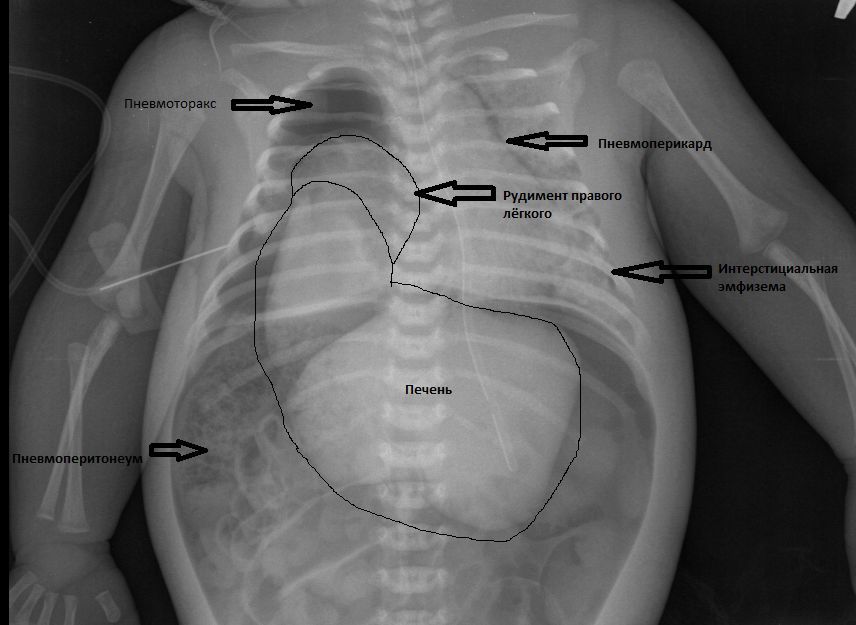

Итак: в данном случае пренатально был выставлена правосторонняя диафрагмальная грыжа, родоразрешение было проведено на республиканском уровне, после чего ребёнком сразу начали заниматься детские хирурги. Была проведена торакоскопия, на которой выявили выраженную гипоплазию и апневматоз правого лёгкого. Кроме того у ребёнка по ходу случилось массивное внутрижелудочковое кровоизлияние и сформировалась прогрессирующая гидроцефалия. В связи с бесперктивноситью оперативного лечения, ребёнок был переведён в РАО нашей больницы в качестве хосписного больного. Поскольку состояние ребёнка относительно стабилизировалось , начали подумывать о возможноти всё- таки провести опративное лечение, но произошло резкое ухудшение состояния ребёнка в связи с тем, что лопнул рудимент правого лёгкого . Получена рентгенологическая картина почти всех возможных вариантов синдрома утечки воздуха, в т. ч. и пневмоперитонеум , поскольку правого купола диафрагмы не было и воздух из плевральной полости заполнил брюшную полость и дал напряжённый пневмоперитонеум:

Была задренирована правая плевральная полость, в первую очередь воздух ушёл из живота. После всех этих проблем ребёнок прожил ещё около 2-х недель. На секции - правосторонняя ложная диафрагмальная грыжа, гипоплазированное безвоздушное правое лёгкое.